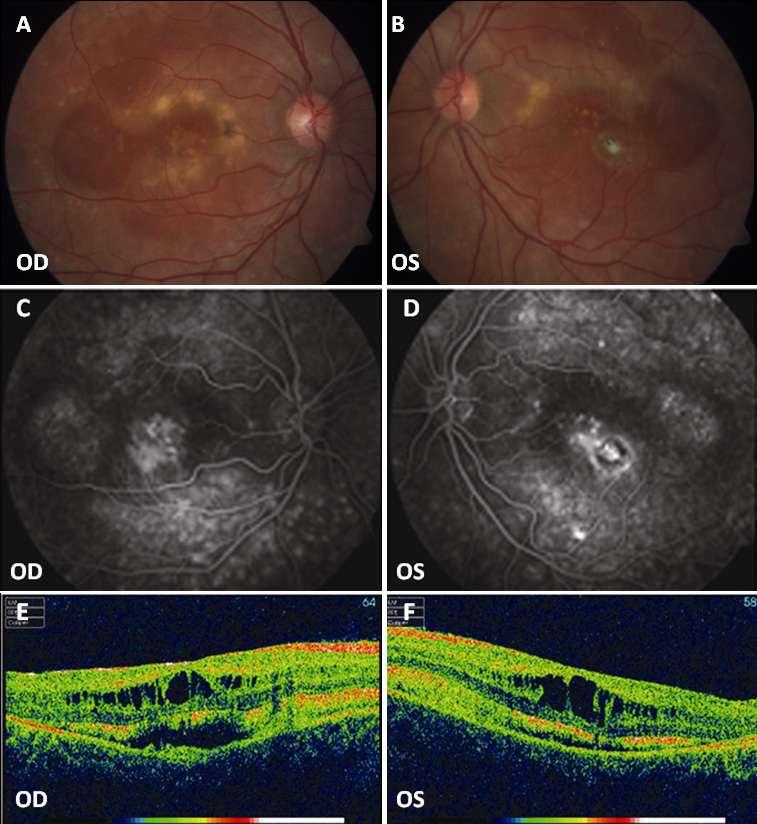

Figure 6. Fundus photographs, fluorescein angiography, and optical coherence tomography (OCT) scans of patient D-3. A, B: Widespread RPE dystrophy and yellowish deposits at the posterior pole with (C, D) bilateral macular hyperfluorescence and small hyperfluorescent spots at the posterior pole and mid-periphery. E, F: Bilateral macular cystoid spaces and two cleavage plans: the outer one between the retinal pigment epithelium (RPE) and

the neuroretina and the inner one below the nerve fibers layer. OD represents the right eye; OS represents the left eye.